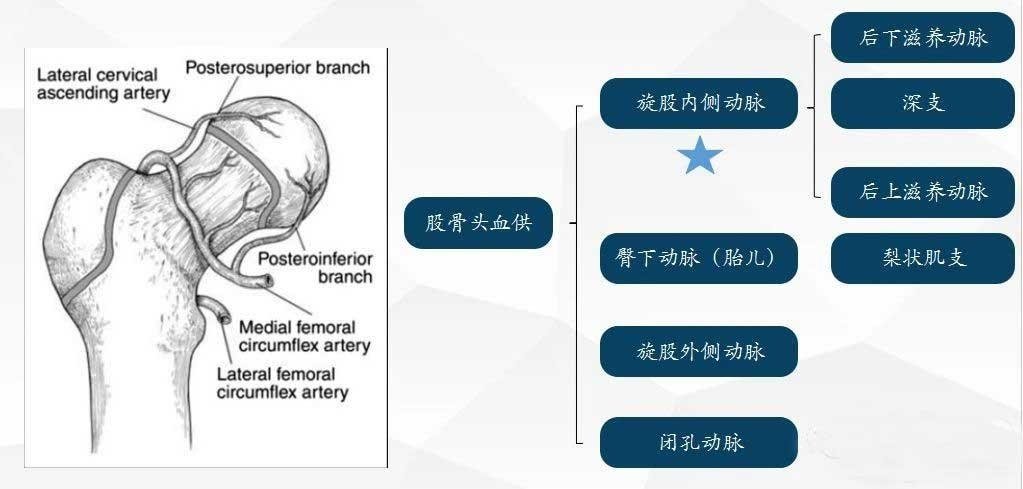

Suministro de sangre a la cabeza femoral

La necrosis avascular de la cabeza femoral está estrechamente relacionada con la irrigación sanguínea de la cabeza femoral La composición de la irrigación sanguínea de la cabeza femoral en niños se ve comúnmente en la siguiente figura.